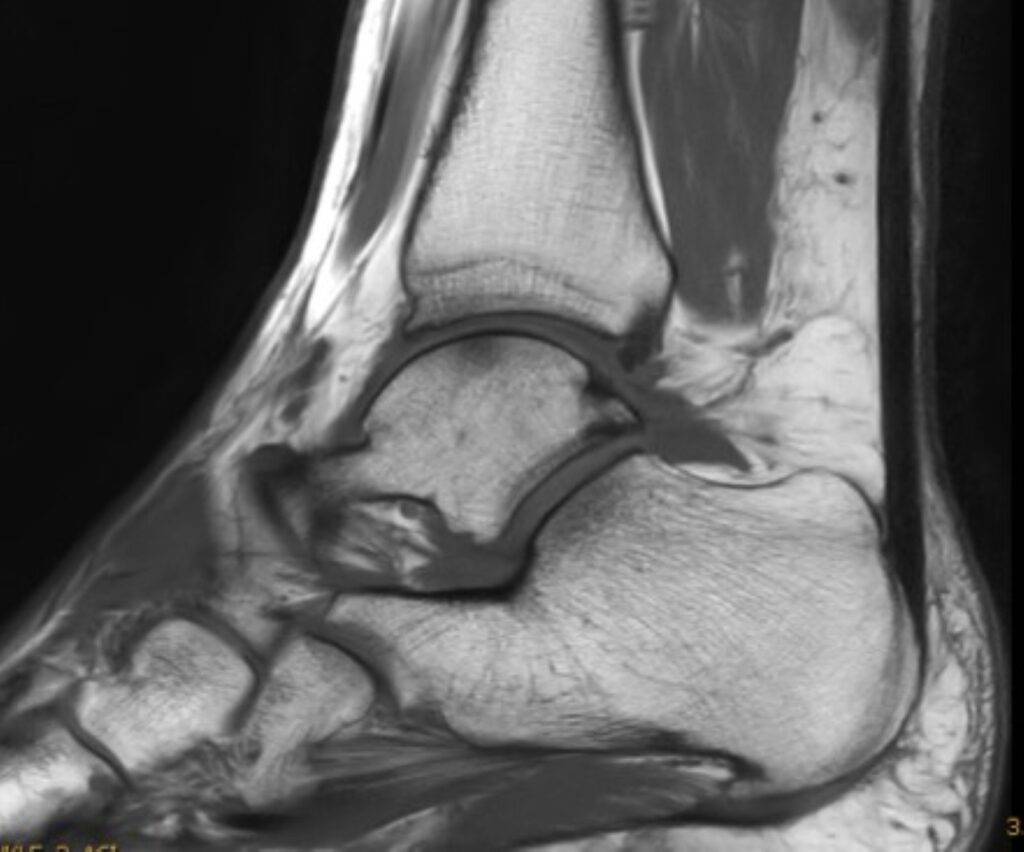

Eine Magnetresonanztomographie des Sprunggelenks, auch MRT Sprunggelenk oder MRT OSG genannt, ist ein bildgebendes Verfahren, das es ermöglicht, das Sprunggelenk mit allen Strukturen präzise und detailliert darzustellen. Die Ursache für Schmerzen oder Schwellungen im Sprunggelenk können durch eine MRT lokalisiert werden.

Das Sprunggelenk setzt sich aus verschiedenen anatomischen Strukturen zusammen, die in einer MRT dargestellt werden können. Dies geschieht durch ein starkes Magnetfeld und Radiowellen. Es werden Querschnittbilder des Sprunggelenks erstellt. Die MRT Bilder des Sprunggelenks dienen später dem Radiologen oder der Radiologin zur Diagnosestellung, damit der behandelnde Arzt oder die behandelnde Ärztin eine entsprechende Therapie ansetzen kann.

- Knochen: Knochenstrukturen, sowie das Sprunggelenk selbst werden in der MRT detailliert dargestellt. Die Unterschenkelknochen (Tibia und Fibula) sind ebenfalls sichtbar.

- Bänder und Sehnen: Das Sprunggelenk wird durch Bänder und Sehnen gestützt und stabilisiert. Kommt es zu Verletzungen oder Entzündungen an diesen Strukturen, kann dies in einer MRT dargestellt werden.

- Knorpel: Ein Teil des Gelenks bildet der Gelenksknorpel. Knorpelabnutzung oder Knorpelläsionen werden in einer MRT abgebildet.

- Weichteile: Muskeln, Faszien und Blutgefäße können ebenfalls Verletzungen erfahren. Dies äußert sich in Form von Schwellungen oder Entzündungen. Die MRT-Untersuchung ermöglicht die Lokalisierung des betroffenen Areals.